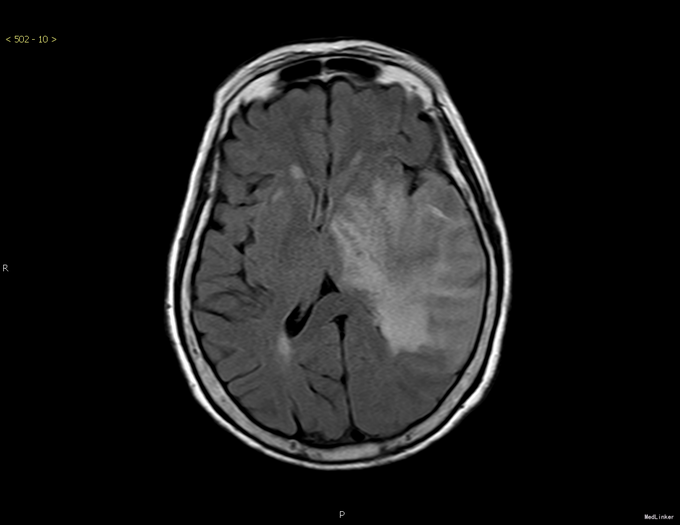

主诉:答非所问1周。 患者1周前无明显诱因下出现答非所问,无发热、寒战,无恶心、呕吐,无头晕、头痛,无四肢抽搐,无昏迷不省。起病以来,患者精神、睡眠、胃纳好,无进行性意识障碍,大小便正常。

查体:神智清晰,精神行为无异常,对答不切题,理解力、记忆力、计算力、定向力、判断力患者未能配合检查。其余无特殊。 头颅CT平扫+增强结果示:左侧颞顶叶占位病变并周围大片水肿。

诊断:原发中枢神经系统淋巴瘤(弥漫大B细胞淋巴瘤,非GCB组) 治疗:入院行立体定向下左颞叶病灶活检术,病理:非霍奇金淋巴瘤,B细胞性,原发中枢神经系统弥漫大B细胞淋巴瘤,非GCB样免疫亚型。予替莫唑胺150mg d1-5口服和第1疗程HD-MTX治疗。